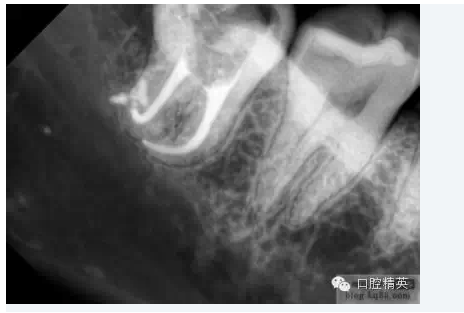

5.根管髓腔部分的預(yù)先擴(kuò)大可以幫助牙醫(yī)做出更明確的診斷。預(yù)先擴(kuò)大的根管髓腔部分可以容納較大型號(hào)的金屬根管擴(kuò)大器,X光片顯示更清晰;由于接觸頭更容易的與髓腔牙本質(zhì)接觸,電子根尖定位器的顯示也更明確。

2.確定根尖孔的合適開(kāi)放根據(jù)X線片(RT)確定的根尖孔位置,將一柔軟的10號(hào)擴(kuò)孔銼輕輕推進(jìn)。為了保證根尖孔的良好開(kāi)放,應(yīng)保證擴(kuò)孔銼尖端超過(guò)根尖孔1mm, 同時(shí)減少齲壞牙本質(zhì)碎霄的堆積 (在10號(hào)擴(kuò)孔銼其D1位置的直徑為0.12mm) ,輕輕的將之向前推進(jìn)1mm,以提供更大的空間,保證所有牙髓組織碎片、齲壞牙本質(zhì)碎霄的清除及沖洗液的自如進(jìn)出,同時(shí)降低根管堵塞的發(fā)生率。根尖孔完全開(kāi)放或10號(hào)擴(kuò)孔銼向前推進(jìn)幅度不足1mm都是不可取的,因?yàn)榕R床研究表明:兩種選擇的治療結(jié)果都不甚理想。